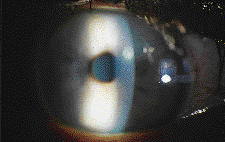

Corneal Bacterial and Fungal Keratitis

Bacterial ulceration (Figs. 9a & 9b) is the most severe and sight-threatening clinical entity associated with contact lens wear. All contact lens wearers have a higher risk for ulceration than non-contact lens wearers, but some risk factors are especially significant. Schein et al. (1989) pointed out that extended wear patients have a risk about 10 times greater than users of daily wear lenses. Other factors that increase the risk for bacterial ulceration in contact lens wearers include: diabetes, cigarette smoking, contaminated solutions and cases, use of topical steroids and reduced tear film. Fungal keratitis is very rare and more closely associated with trauma than with contact lens wear, but as Wilson and Ahearn pointed out in the American Journal of Ophthalmology (1996), contact lens wear can be associated with corneal and conjunctival fungal infection.

|

When a contact lens patient presents with acute inflammation and evidence of corneal infection, it's important for you to determine whether the patient has corneal ulceration or a less serious condition. Corneal infiltrates may mimic the appearance of an early ulcer. Contrary to what many practitioners believe, staining of an infiltrative lesion is not diagnostic of ulceration. Sterile ulcers may subsequently lose their overlying epithelium and stain with fluorescein. Infectious keratitis usually results in a 360-degree limbal response. In contrast, non-ulcerative infiltrates usually have focal injection in the quadrant where the lesion is located. Patients with bacterial ulcers often present with significant anterior chamber activity or frank hypopion. Non-infectious infiltrates rarely cause significant anterior chamber activity. Infiltrates rarely obscure underlying iris details, but ulceration frequently makes visualization of the iris anatomy difficult.